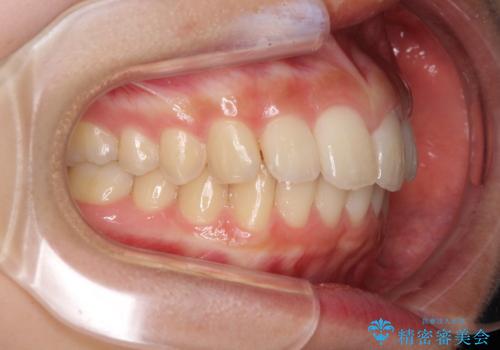

就職前にきれいな歯並びにしたい 大学生のインビザライン矯正

- 就職するまでに歯並びをきれいにしたいとのことで来院された患者様です。

前歯の叢生を気にしていましたが、極力突出感を改善できるようにすることとし、インビザラインにて矯正治療を行うこととしました。

改善の期待できない口元の突出感改善を希望されたため、いたずらに治療期間が延びましたが、きっちりと仕上がりました。